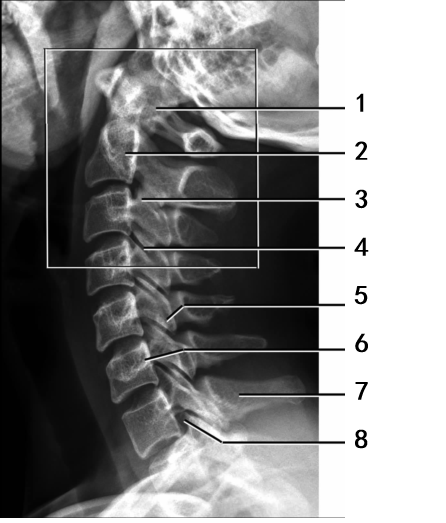

第二节 颈部的 X 线解剖和血管影像解剖

掌握颈部软组织的侧位X 线解剖,熟悉颈部的血管造影。了解其他影像解剖。